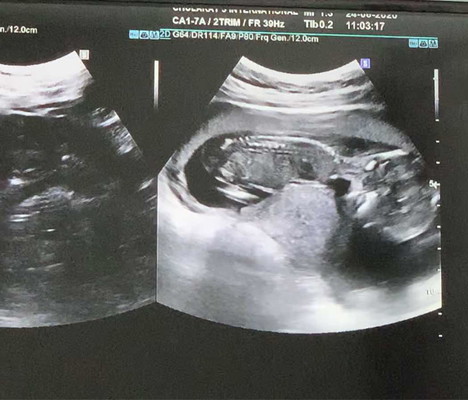

มาแชร์ภาพอัลตราซาวด์ ทีมธันวาคา อยากทราบว่าแม่ๆ กำหนดคลอดวันไหน และตั้งครรภ์ได้กี่สัปดาห์กันแล้วคะ 🥰🥰🥰

17+6w คะ กำหนดคลอด11 ธันวาคม ช่วยดูหน่อยว่าผู้หญิง หรือชาย

บ้านนี้14สัปดาห์บวกอีก6วัน กำหนดคลอดลูก29ธันวาคม ค่ะ

ตอนนี้ 16 สัปดาห์ + 4 วันคร๊า ครบกำหนด 17 ธค ค่ะ

ตอนนี้ 17w 1d ค่ะ กำหนดคลอด 13 ธันวาคม ได้ลูกชายคะ 😍

กำหนดคลอด 16 ธันวาคม 63 😍บ้านนี้ได้ลูกสาวค่า 👸👸

ตอนนี้16วีคค่ะ กำหนด21ธ.ค.ค่ะ นัดซาวท้อง22ก.ค

ทีมธันวาเหมือนกันค่ะ กำหนดคลอด 9 ธันวา

คลอด14 ธันวา ตอนนี้ได้17สัปดาห์1วัน แล้วคะ